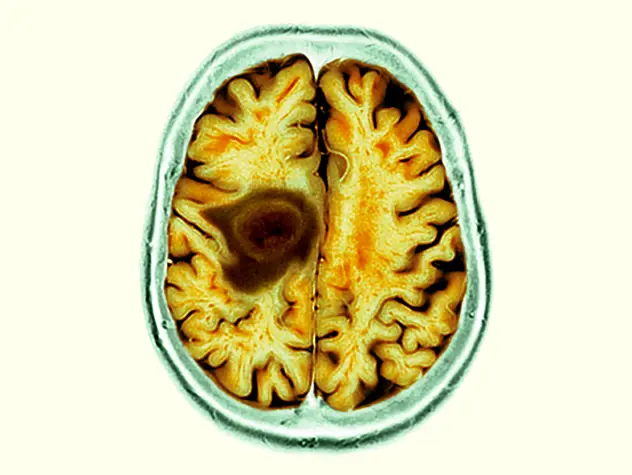

Through two world-class cancer centers – Columbia’s NCI-designated Herbert Irving Comprehensive Cancer Center and Weill Cornell Medicine’s Meyer Cancer Center, our team of physician-scientists are transforming care for cancer patients across a broad spectrum of malignant diseases and conditions. From pursuing novel laboratory research to better predict, diagnose and treat cancer, to conducting clinical trials of promising new therapies, our physicians provide personalized treatment plans to deliver optimal outcomes.